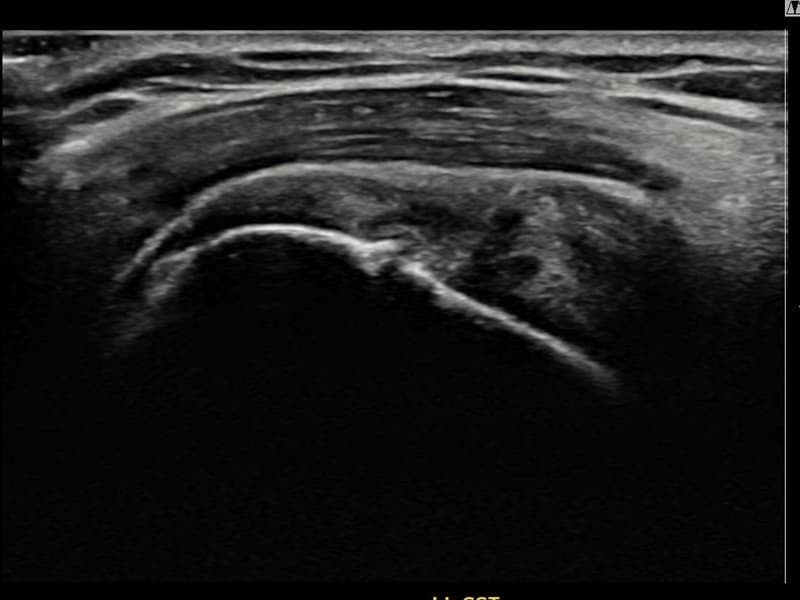

术前

术前超声确认左侧 冈上肌腱 关节面侧部分撕裂,左侧冈上肌腱回声不连续伴肌腱缺损(8mm × 3mm (肌腱厚度约30%缺损))。术后超声显示撕裂部位充满再生组织,肌腱连续性恢复,回声模式正常化。